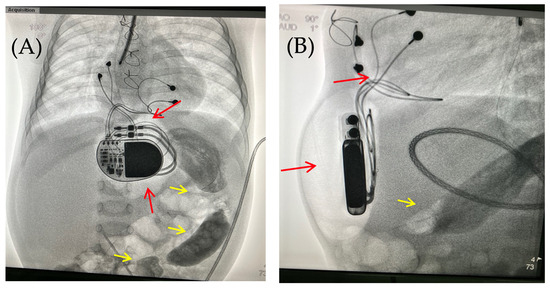

On the 8th postoperative day, the wound healed by primary intention. During pacing programming, impedance values, atrial and ventricular pacing thresholds were satisfactory; no pacing abnormalities were detected. On the 10th postoperative day, local examination in the upper anterior abdominal wall along the midline revealed a localized bulge of skin and soft tissue in the projection of the pacemaker pocket (Figure 1).

Figure 1. Thoracoabdominal view. Lateral (A) and frontal (B) views. A mass and soft tissue bulge are noted (red arrow) in the area of the pacemaker pocket in the subxiphoid region of the anterior abdominal wall, limited by the projection of the pacemaker body.